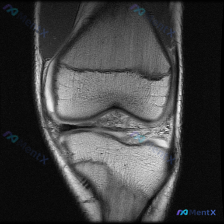

今天遇到一个挺有代表性的病例,主诉提示膝关节半月板异常,只提供了单张膝盖MRI冠状位T1加权像,整理一下分析思路跟大家分享。 一、病例核心信息 核心问题:患者主诉提示半月板异常,仅提供单一层面冠状位T1加权MRI读片 影像观察结果: 1. 骨骼:股骨远端、胫骨近端骨皮质完整连续,骨髓腔T1信号为均匀...